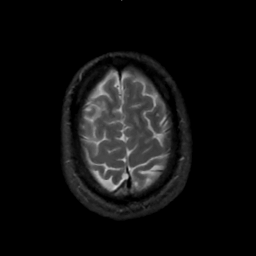

MR Study #1, February 10, 1991 -- Slice #43

[Home][Help][Clinical][Tour 1][Tour 2] Slice 43